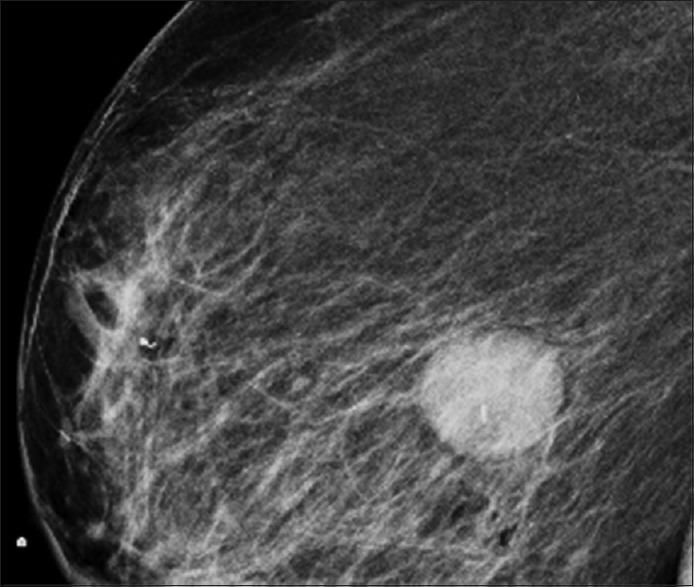

Malignant peripheral nerve sheath tumors (MPNSTs) are extremely rare soft tissue sarcomas of ectomesenchymal origin. They are commonly seen in association with neurofibromatosis type 1 (NF-1), but can also occur without a history of NF (isolated MPNST). MPNSTs are most commonly located on the extremities (brachial and sacral plexus), head and neck, and trunk regions and are rarely reported in genitourinary organs. These tumors are aggressive, with a high recurrence rate and distant metastases. MPNST involving the kidney is extremely rare, and review of the literature using PubMed from 2001 to 2014 revealed eight cases of MPNST involving the kidney (seven, primarily involving the kidney and one metastatic MPNST of the kidney). Herein, we describe a case of breast metastases from an MPNST of the kidney without a history of NF-1. The patient was initially diagnosed with a spindle cell neoplasm of the kidney with peripheral nerve sheath differentiation. Eventually, the patient developed a right breast mass that was diagnosed as metastatic MPNST. The patient refused any kind of treatment and died 6 months later in hospice care.

恶性外周神经鞘瘤(MPNSTs)是起源于外胚间叶组织的极为罕见的软组织肉瘤。它们通常与1型神经纤维瘤病(NF-1)相关,但也可在无NF病史的情况下发生(孤立性MPNST)。MPNST最常见于四肢(臂丛和骶丛)、头颈部及躯干区域,很少报道发生于泌尿生殖器官。这些肿瘤具有侵袭性,复发率高且易发生远处转移。累及肾脏的MPNST极为罕见,使用PubMed对2001年至2014年的文献进行回顾,发现有8例累及肾脏的MPNST(7例主要累及肾脏,1例为肾脏转移性MPNST)。在此,我们描述1例无NF-1病史的肾脏MPNST发生乳腺转移的病例。该患者最初被诊断为具有外周神经鞘分化的肾脏梭形细胞瘤。最终,患者出现右侧乳腺肿块,被诊断为转移性MPNST。患者拒绝任何治疗,6个月后在临终关怀中死亡。